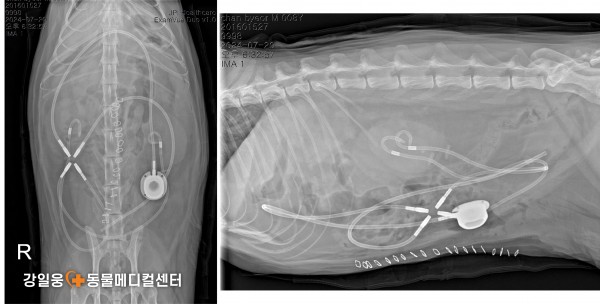

고양이 요관 폐쇄, SUB 수술로 새로운 길을 열다

SUB 수술(Subcutaneous Ureteral Bypass)

SUB 수술(Subcutaneous Ureteral Bypass) 은

요관이 막혔을 때 신장에서 방광으로 새로운 우회로

(인공 튜브)를 만들어 소변이 원활히 배출되도록 돕는 수술입니다.

쉽게 말해, 막힌 도로(요관)

대신 새로운 길을 만들어

신장에 고여 있던 소변이 다시 정상적으로

방광으로 내려가게 하는 수술입니다.

⚠️ 수술 후 주의 사항 및 예후

SUB 수술은 고양이의 요관 폐쇄에 대한 표준 치료법으로 자리 잡고 있지만,

감염, 튜브 막힘, 장치 손상, 누출 등 다양한 합병증이 생길 수 있습니다.

또한 대부분의 환자들이 이미 신장 데미지가 있는 상태에서 수술을 받기 때문에

수술 후 만성 신부전(CKD) 관리가 함께 필요합니다.

강일웅동물메디컬센터 정형·신경외과 전승하 원장은

그동안 다양한 원인으로 요관이 막힌 고양이들을 치료하며

여러 형태의 SUB 수술 사례들을 해결해 왔습니다.